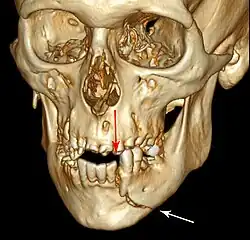

This injury involves the alveolar bone and may extend beyond the alveolus.[5][6] There are five different types of alveolar fractures:

- Communicated fracture of the socket wall

- Fracture of the socket wall

- Dentoalveolar fracture (segmental)

- Fracture of the maxilla: Le Fort fracture, zygomatic fracture, orbital blowout

- Fracture of the mandible

Trauma injuries involving the alveolus can be complicated as it does not happen in isolation, very often presents along with other types of tooth tissue injuries.

Signs of dentoalveolar fracture:

- Change to occlusion

- Multiple teeth moving together as a segment and are normally displaced

- Bruising of attached gingivae

- Gingivae across the fracture line often lacerated

Investigation: Require more than one radiographic view to identify the fracture line.

Treatment: Reposition displaced teeth under local anaesthetic and stabilise the mobile segment with a splint for 4 weeks, suture any soft tissue lacerations.